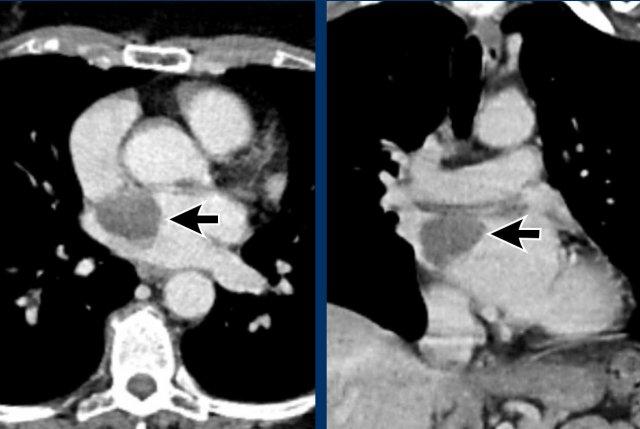

Hình ảnh

Nhĩ trái giãn.

Có huyết khối trong tiểu nhĩ trái (mũi tên) lan rộng về phía nhĩ trái (đầu mũi tên).

Tại tiểu nhĩ trái, thường gặp khó khăn trong chẩn đoán phân biệt hình ảnh giữa huyết khối và hiện tượng ngấm thuốc không hoàn toàn do dòng chảy chậm, đặc biệt khi chụp ở thì thuốc sớm.

Vấn đề này có thể được giải quyết bằng cách chụp CT ở thì thuốc muộn hơn hoặc chụp ở tư thế nằm sấp.

Siêu âm tim qua thực quản được coi là tiêu chuẩn vàng.

Xảo ảnh dòng chảy chậm trong tiểu nhĩ trái, với hình ảnh ngấm thuốc không hoàn toàn của tiểu nhĩ trái ở thì sớm nhưng lấp đầy hoàn toàn ở thì thuốc muộn hơn.